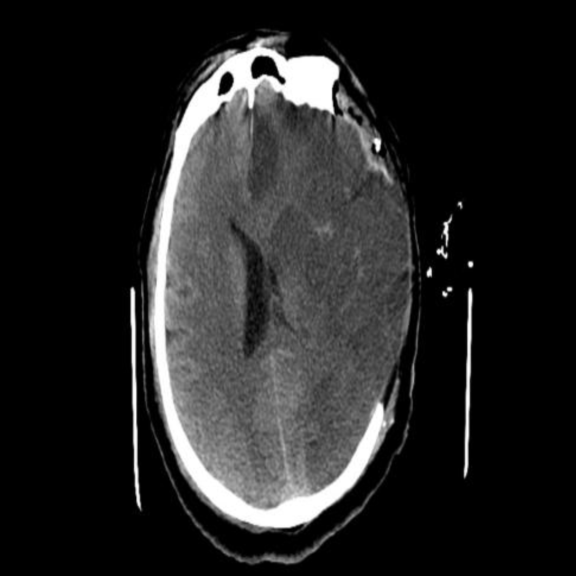

完善颅脑磁共振:

1.DWI示左侧额叶、颞叶及顶叶急性梗死灶。FLAIR示左侧大脑半球未见明显显影。FLAIR及DWI不匹配。

术前DWI